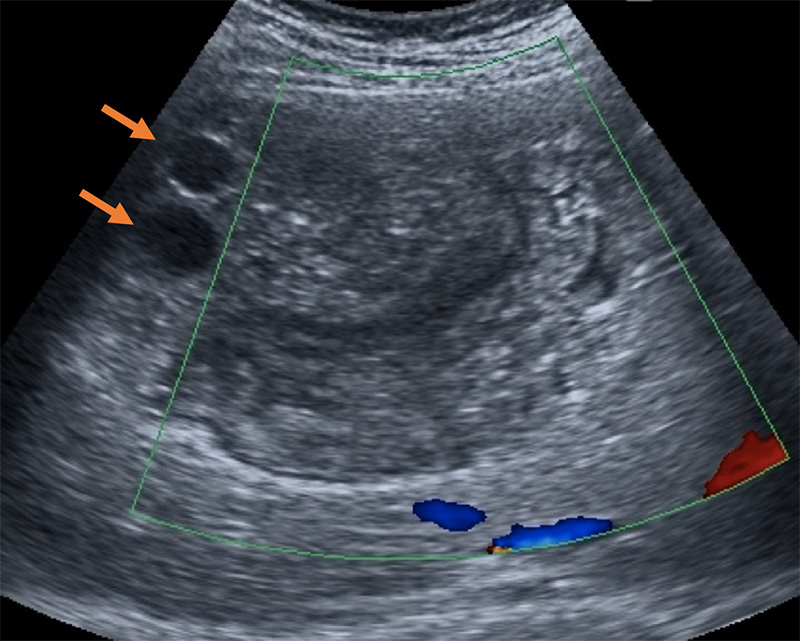

- Thickening, irregularity, or mass of bladder wall

Figure 48. Ultrasonography images of urinary bladder of [School-Aged Children] infected with S. haematobium. a) Thickening of the bladder wall, transverse plane shows thickening of the left lateral wall (arrows); b) Diffuse thickening of the bladder wall more evident in the right posterior wall, echogenic snow in the lumen; c) In oblique longitudinal plane, ultrasound image shows a mass-like lesion in the mucosa layer of the bladder. Block arrow indicates the dilation of the ureter; d) longitudinal plane shows a marked and diffuse thickening of the bladder wall with a mass-like lesion (arrow); e) Mass-like lesion in the absence of a marked and diffuse thickening of the bladder wall; f) Multifocal thickening of the wall, particularly evident on the right and posterior wall. (Reproduced with permission, PLOS https://doi.org/10.1371/journal.pntd.0005400.g003 )